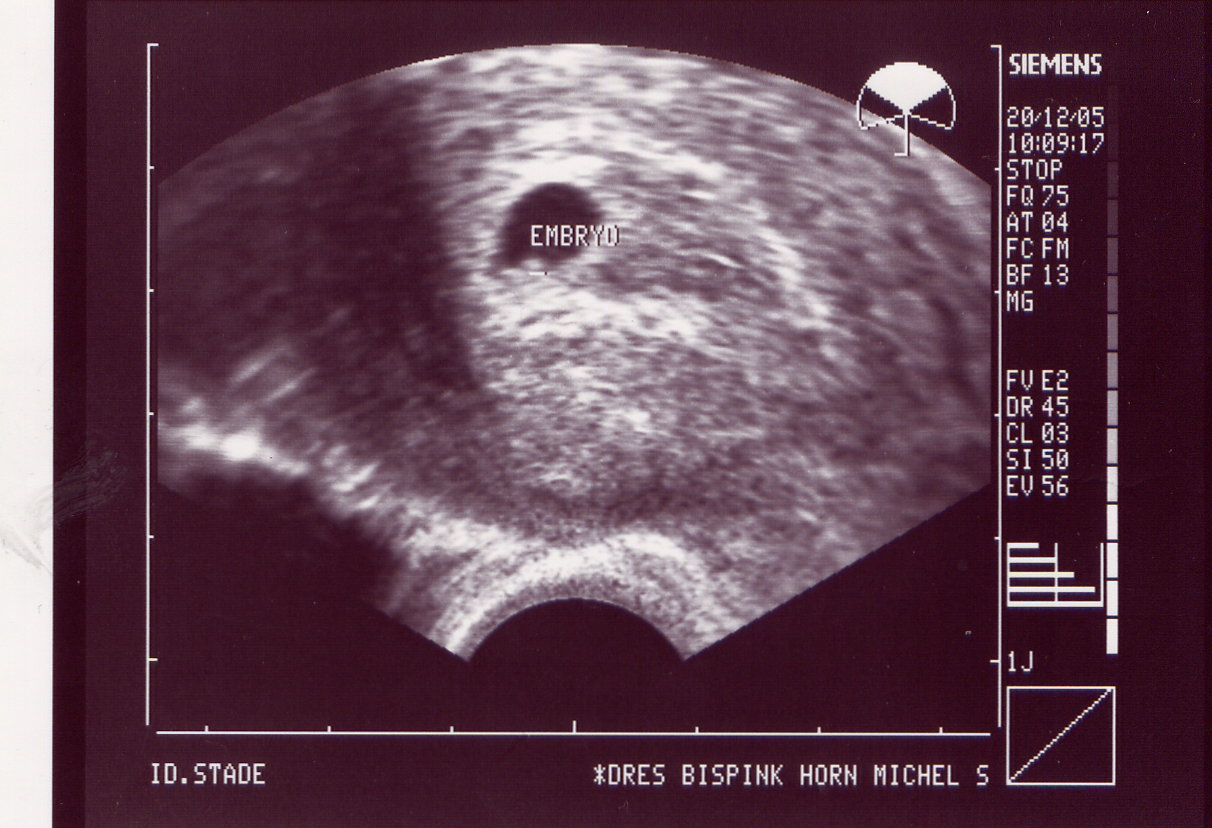

13.12.05 1 Fruchthöhle sichtbar 5+0 HCG 627

20.12.05 Herzchen schlägt 6+0 HCG 3853